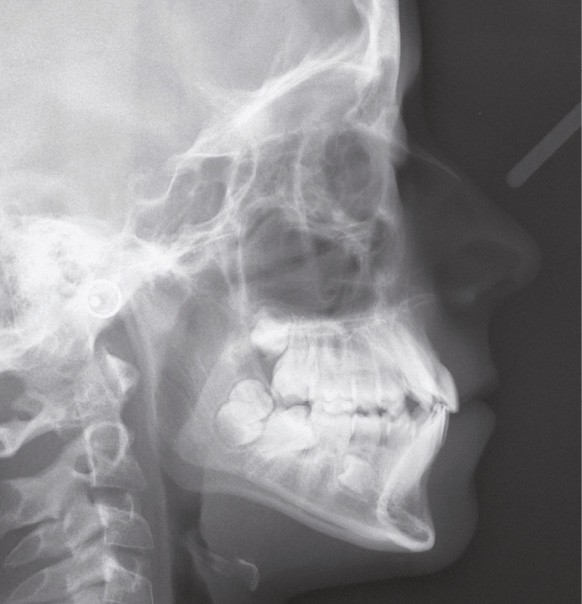

L’examen fonctionnel révèle une déglutition dysfonctionnelle qui n’est pas associée à des troubles ventilatoires ni à des problèmes ORL. Cela explique sans doute que l’examen téléradiographique soit quasi normal, puisque la croissance est harmonieuse à la fois dans la dimension sagittale et dans la dimension verticale (fig. 1f).